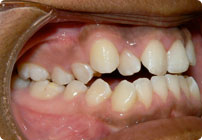

Antes

Caso: 11 años

Adolescente: Clase II

Mordida Cruzada Posterior

Sin extracción

Sin uso de expansores

6 alambres superiores

5 alambres inferiores

Sin uso de elásticos

Retenedores: Interior Fijo de TMA y Hawley en superior

Tiempo de tratamiento: 14 Visitas